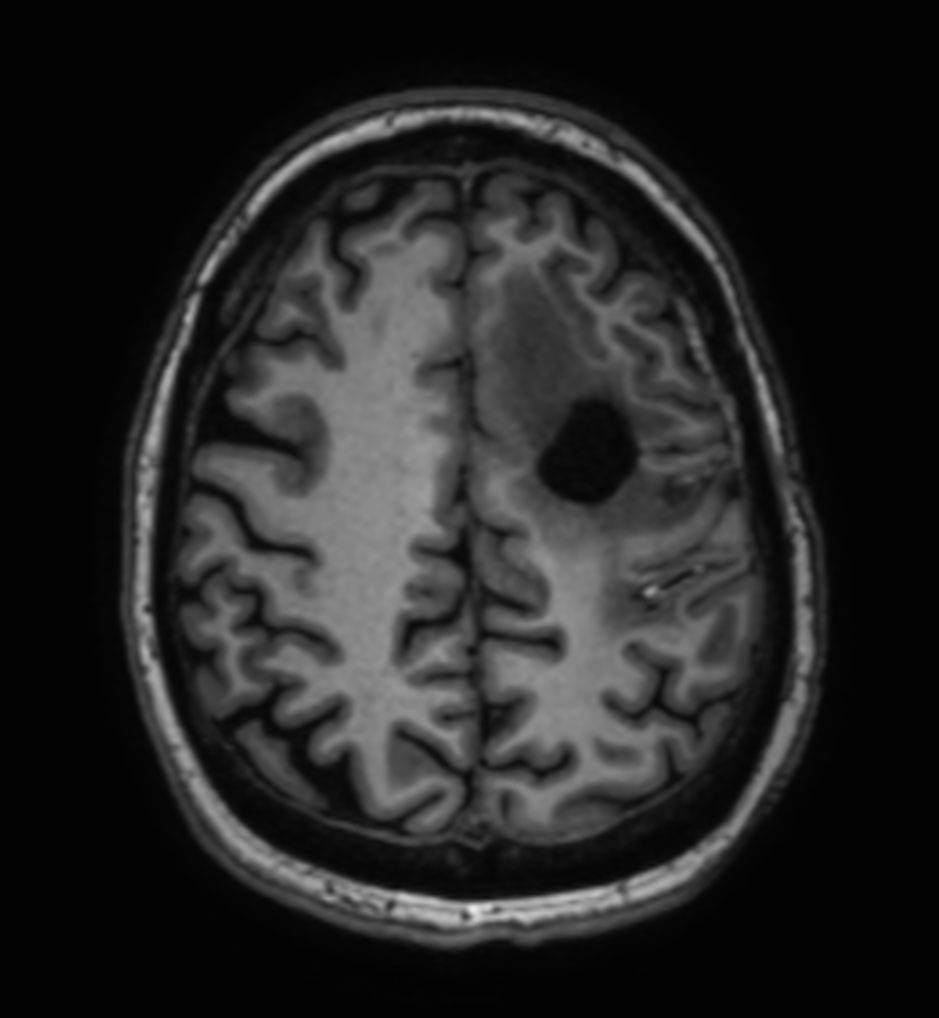

Sagittal 3D T1w TFE

-

3D T1w TFE - Coronal reformat

3D T1w TFE - Axial reformat